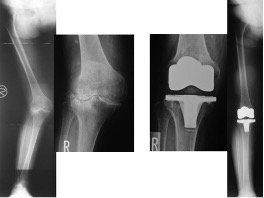

TKAはおもにOA(図2,3)やRA(図4)、UKAは骨壊死(図5)やOAの内側罹患例に行います。左右罹患例には両膝同日手術も施行しています(図3)。手術の目的は除痛、膝関節機能の回復によるADL、QOLの改善です。

人工膝関節は多機種ありますが、当科では自家組織(骨や靭帯)温存に配慮して、主に前十字靭帯のみ切除するCR型を選択し、膝蓋骨は非置換、セメントレス用コンポーネントを用いています(図2)。後療法は両側例でも翌日から離床と荷重を許可し、入院加療は約2週間です。

図2 片側TKA

図3 両側OAに対する両側同日TKA

図4 RAに対するTKA

図5 大腿骨内側顆部骨壊死に対するUKA